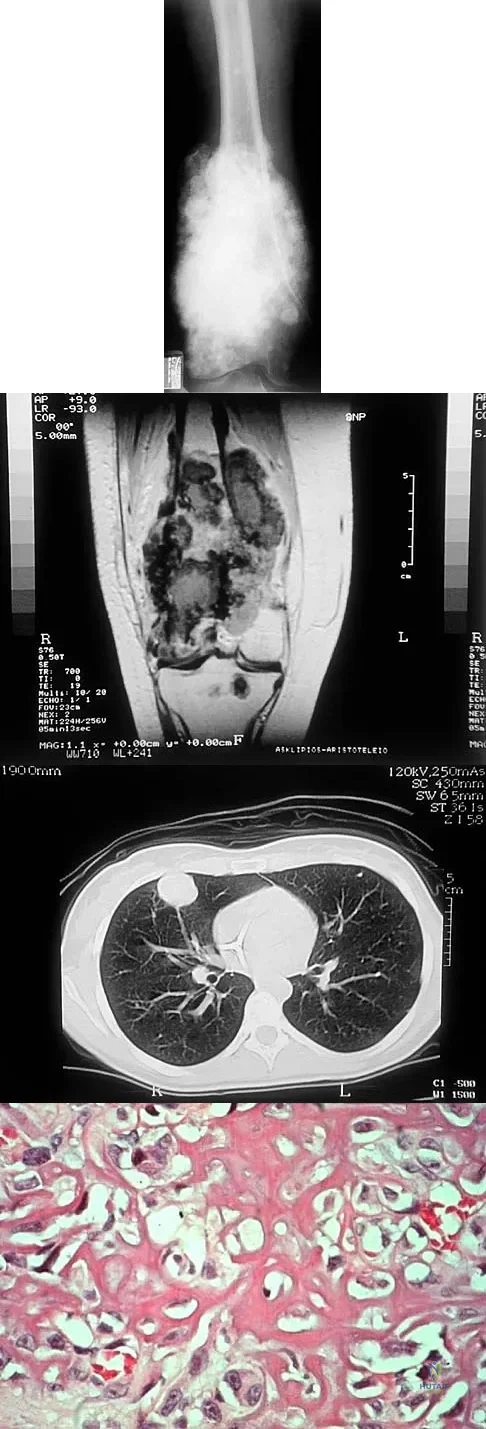

Question 16

A 15-year-old girl reports a 6-month history of activity-related knee pain and swelling. A radiograph, MRI scan, and biopsy specimen are shown in Figures 21a through 21c. What is the most likely diagnosis?

Explanation

Question 17

A 19-year-old woman has a painful right knee. A radiograph, MRI scan, CT scan, and histopathologic specimen are shown in Figures 24a through 24d. What is the most likely oncologic stage of the lesion?

Explanation